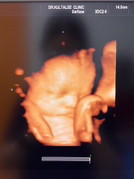

ลูกชาย อัลตร้าซาวด์ตอน 34 week ค่ะ